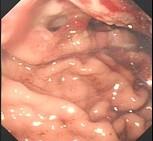

问题 患者,男性50岁,近2个月来出现中上腹隐痛,餐后更甚,伴早饱、厌食,乏力,无发热、黄疸,体重减轻了5Kg,大便隐血阳性,胃镜检查如图,则该患者最可能的诊断是 ( )

选项 A、胃癌 B、食管癌 C、消化性溃疡 D、胃溃疡出血 E、慢性胃炎

答案 A